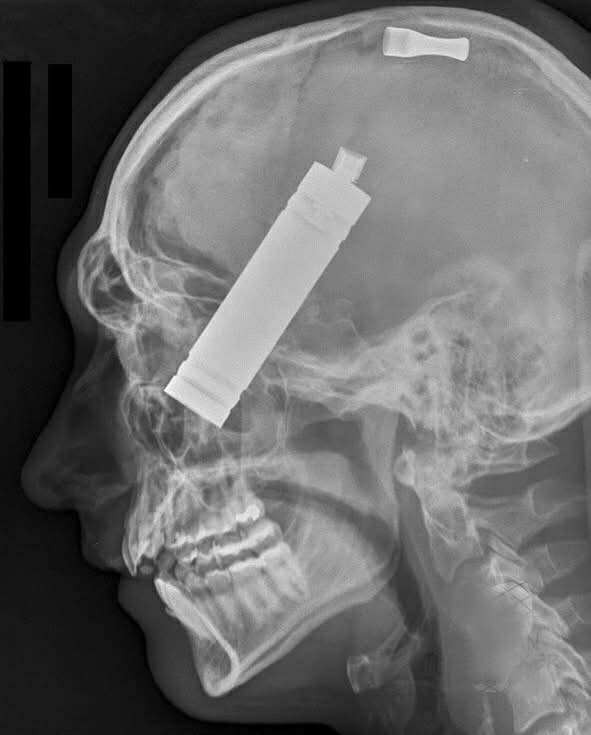

Soused později hlásil: „Slyšel jsem lupnutí, jako výstřel. Pak prasknutí. Plameny už byly v oknech.“ Když hasiči vtrhli do domu, kouř byl tak hustý, že jím nepronikly ani baterky. Na podlaze ležela roztříštěná vaporizérová cigareta a dva kovové úlomky byly později nalezeny… v lebce majitele.

Rentgen odhalil, že k explozi došlo přímo vedle jeho obličeje. Oheň zachvátil jeho polštář, záclony a stěny. Podle pitvy utrpěl D’Elia popáleniny na 80 % těla. Ani se nestihl zvednout. Všechno se to stalo během několika sekund.